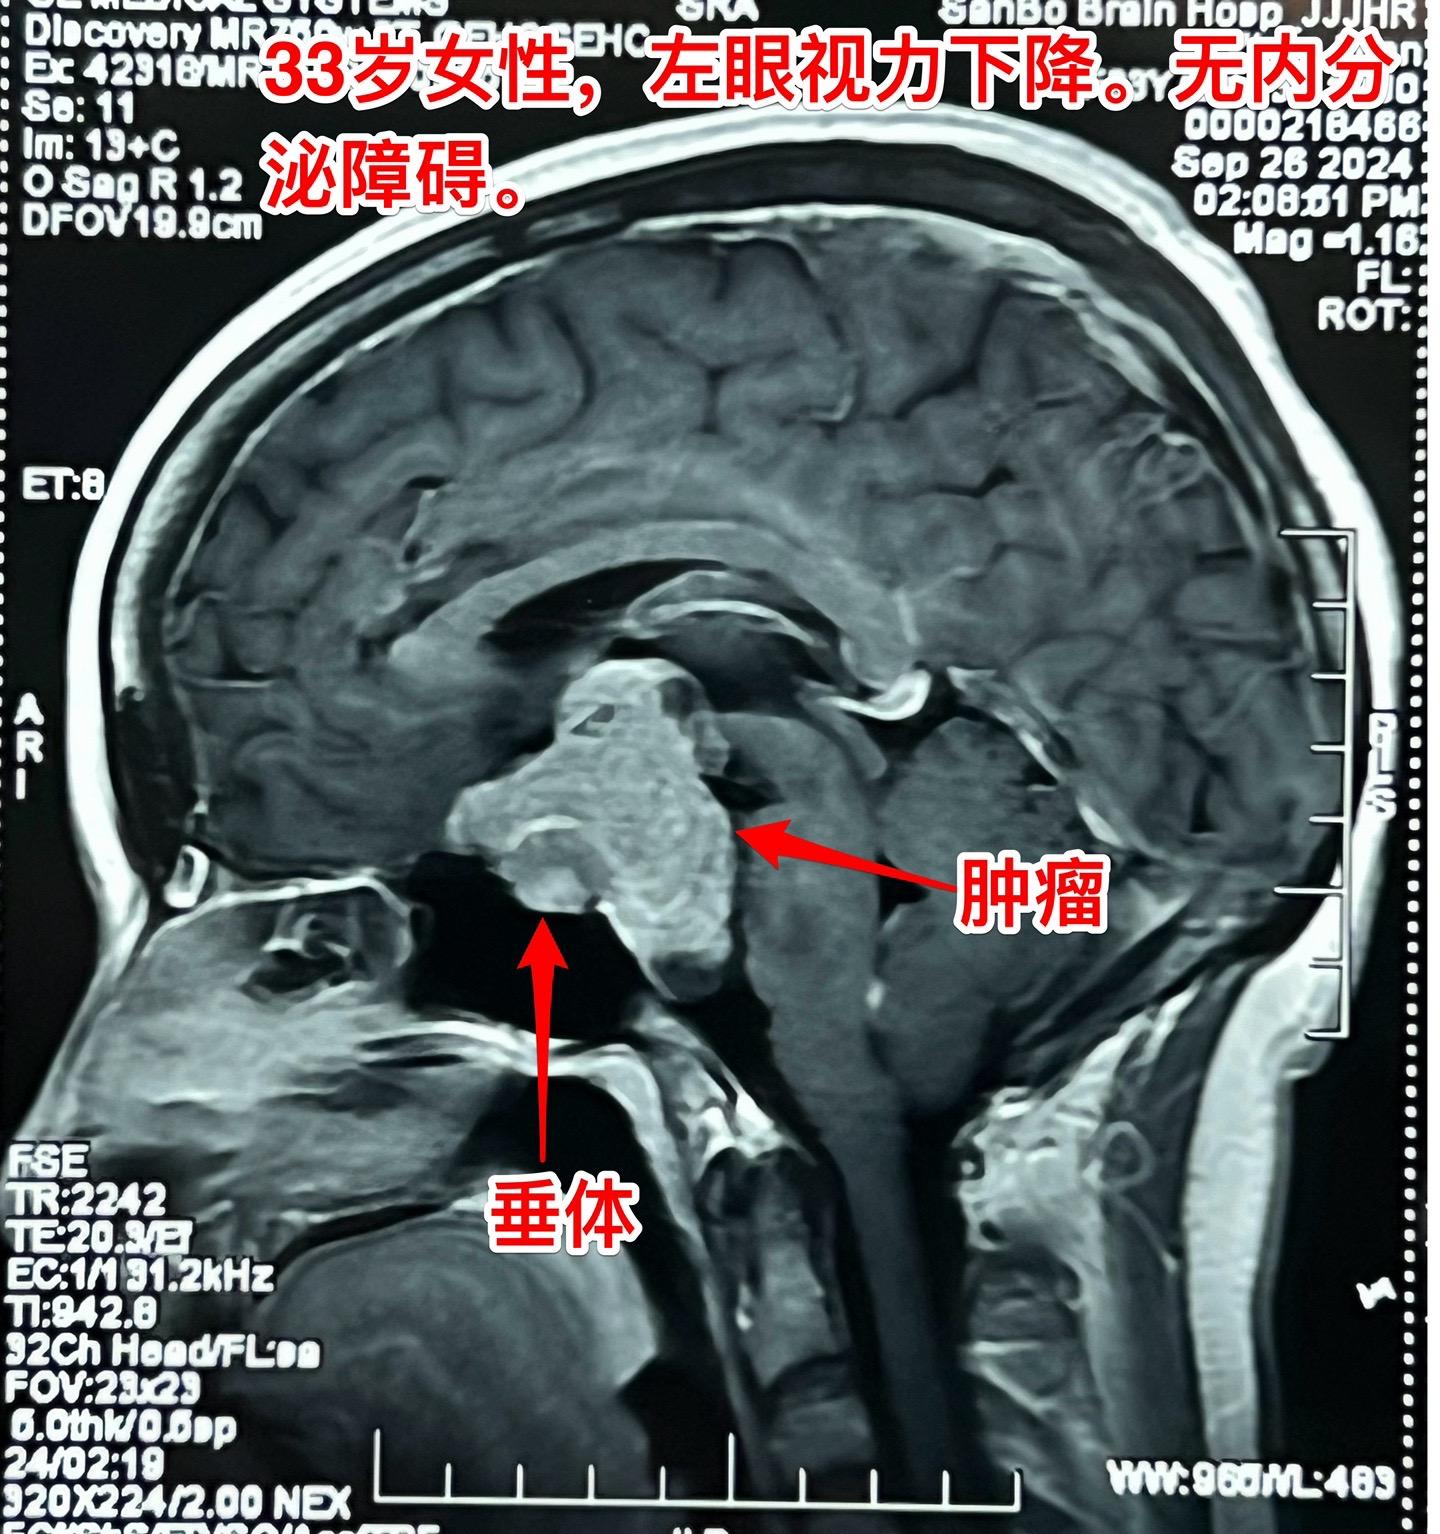

国庆节长假后第一天完成两个手术。一个手是33岁女性,来自云南省香格里拉。因左眼视力下降,到医院检查发现鞍区肿瘤,怀疑是颅咽管瘤。病人没有内分泌功能障碍。影像学上肿瘤是实性的,没有钙化,而且可以看见垂体信号。到底是什么肿瘤呢?今天手术中取肿瘤标本作快速冰冻病理检查,报告是垂体瘤。肿瘤得到完全切除,手术后病人视力好转了。 另一个手术是11岁男孩子,颅咽管瘤复发。经原切口翼点入路将肿瘤完全切除。术前磁共振只看见一个圆形肿瘤,术中发现除了这个肿瘤外还有5个散在的钙化斑,均得到完全切除。这样的散在钙化斑是潜在的危险因